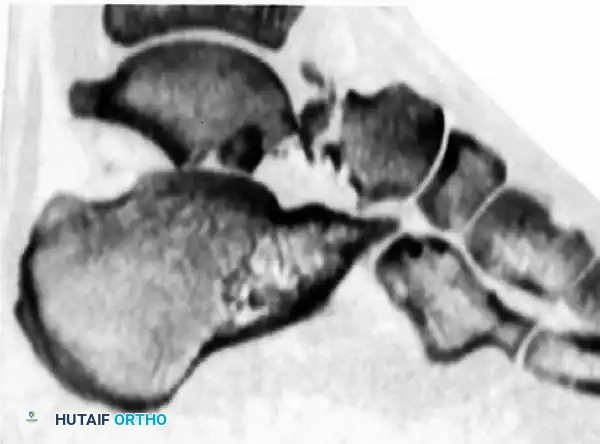

Computed Tomography (CT)

A fine-cut CT scan with sagittal and coronal reconstructions is the gold standard for preoperative planning. It delineates fracture lines, identifies intra-articular step-offs, and reveals concomitant injuries such as lateral process fractures or subtalar debris.